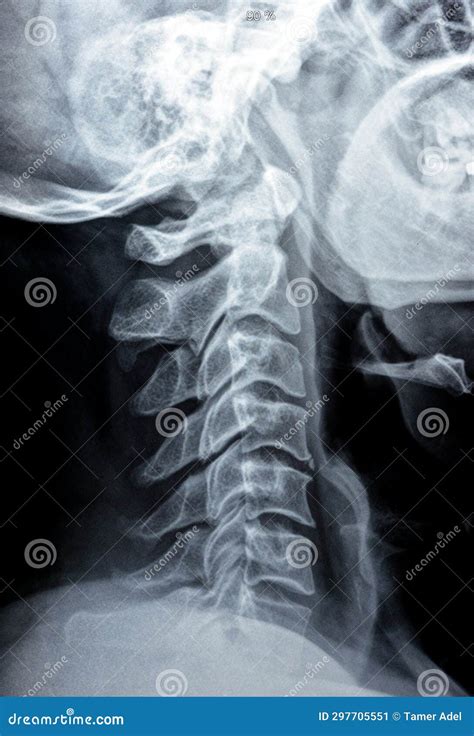

Diagnosis and Imaging

If you suspect you have a straight cervical spine, a physical examination by a chiropractor, physical therapist, or orthopedic specialist is the first step. They will check for muscle imbalances and range of motion restrictions. However, to confirm the loss of curvature, medical imaging is necessary:

• Lateral Cervical X-ray: The most common method to view the curvature of the spine from a side profile.

• MRI (Magnetic Resonance Imaging): Used if your doctor needs to check for damage to the intervertebral discs or spinal nerves.